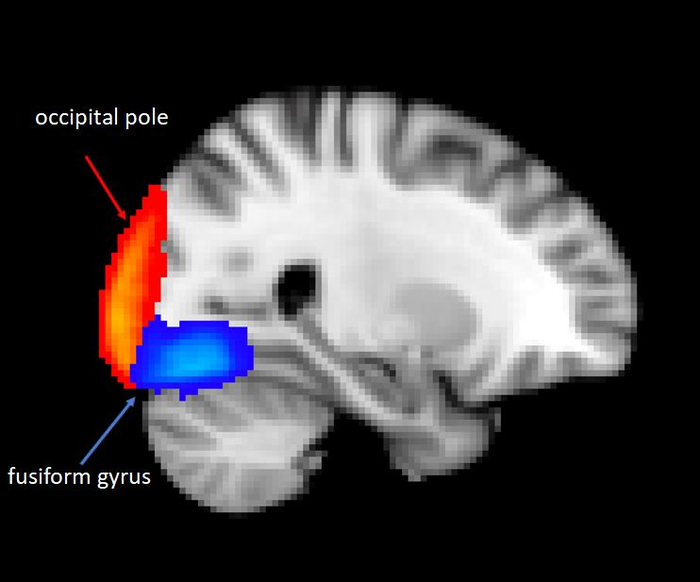

The researchers, from the University of Oxford, compared brain activity of 29 depressed adolescents with that of 16 healthy adolescents, aged 13 to 18. They found that when depressed adolescents were shown a series of photos of distressing images, there was reduced activity, as shown on an fMRI brain scan, (compared to non-depressed adolescents) in brain areas related to visual processing; the occipital pole (which processes visual information, found at the rear of the brain) and the fusiform gyrus (which is involved in the processing of faces, body and colours, found near the brain stem and cerebellum). The images depicted scenarios such as someone crying, someone visibly hurt, someone being attacked.